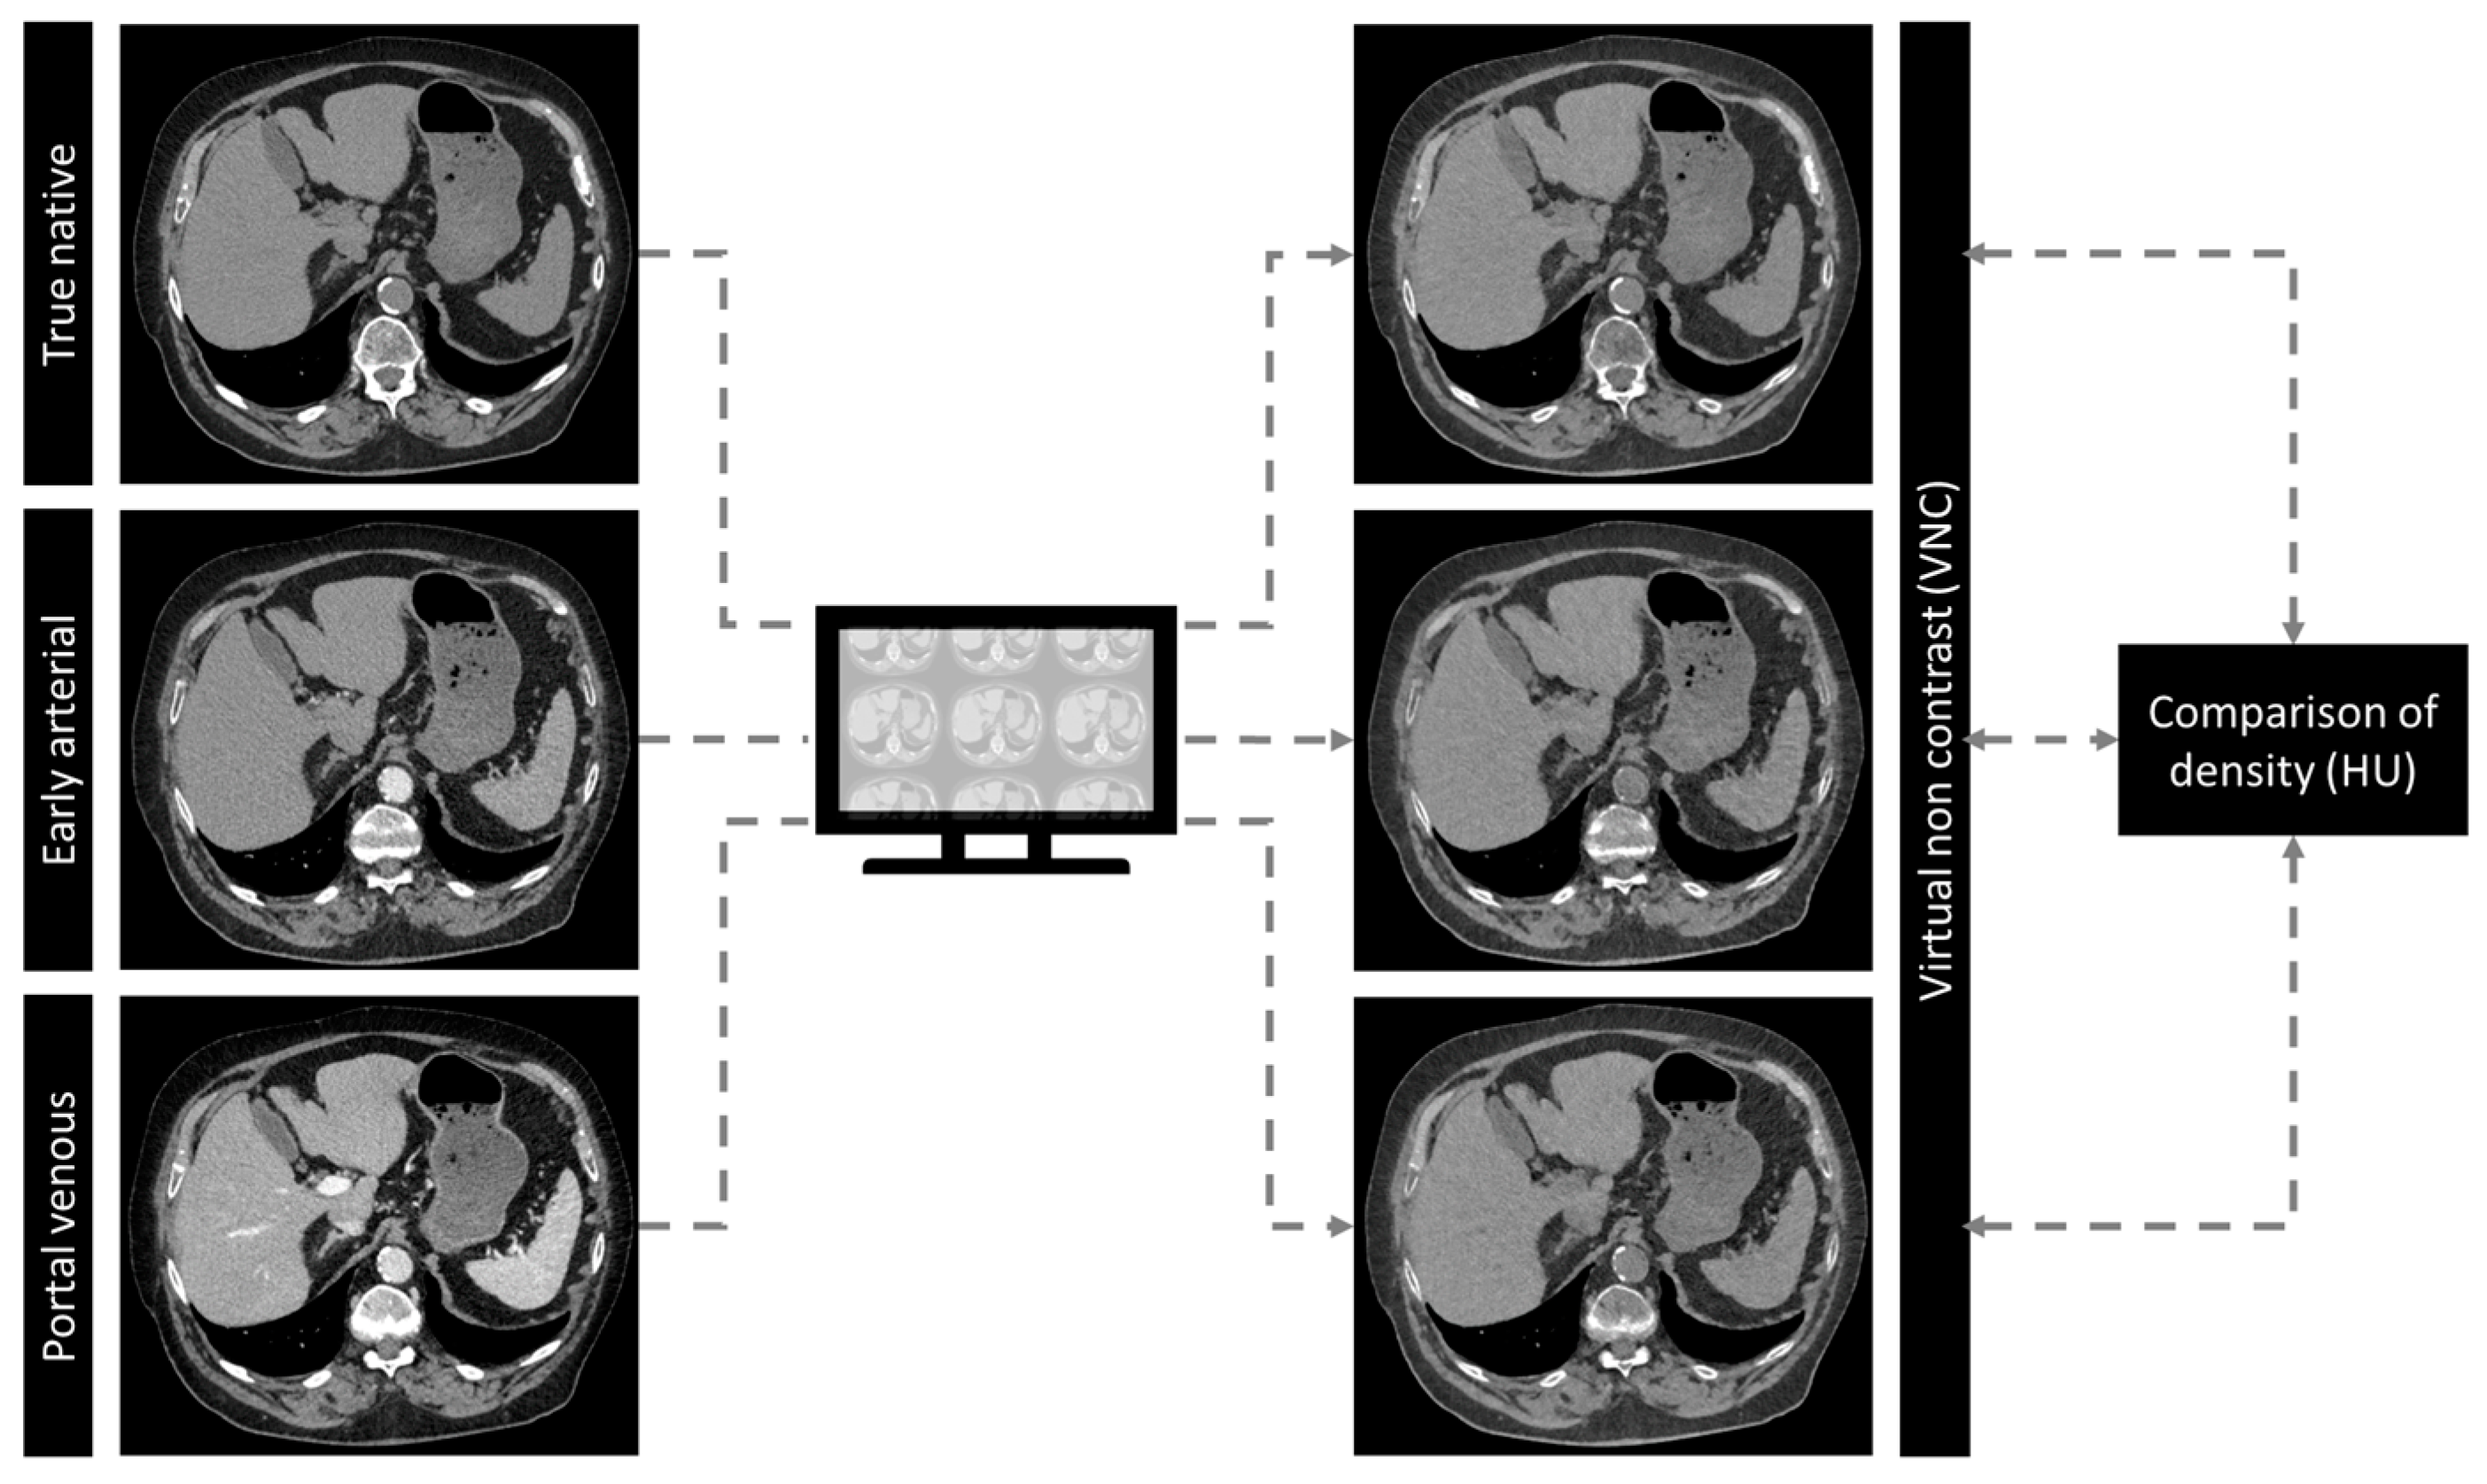

2. Materials and Methods

2.2. CT Scan and Contrast Protocol

2.3. Structured Measurements